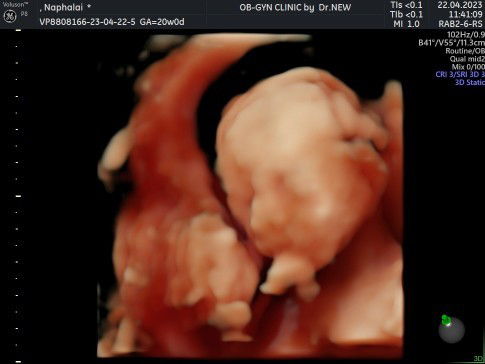

สอบถามแม่ๆหน่อยค่ะอยากทราบว่าปกติแล้วคุณหมอจะให้เราตรวจค่าน้ำตาลกันตอนช่วงเราตั้งครรภ์กี่เดือนคะ ตอนนี้เราตั้งครรภ์จะครบ6เดือนแล้วยังไม่เห็นคุณหมอบอกเลย แต่แม่น้ำหนักไม่ค่อยขึ้นแบบนี้เกี่ยวกับที่คุณหมอยังไม่ตรวจไหมคะ น้ำหนักขึ้นมาจากตอนก่อนท้อง 3 โล แต่น้องน้ำหนักตามเกณฑ์ปกติค่ะ ##ขอบคุณล่วงหน้านะคะ #ขอคำแนะนำหน่อยค่ะ #ขอบคุณสำหรับคำตอบค่ะ #ท้องแรก